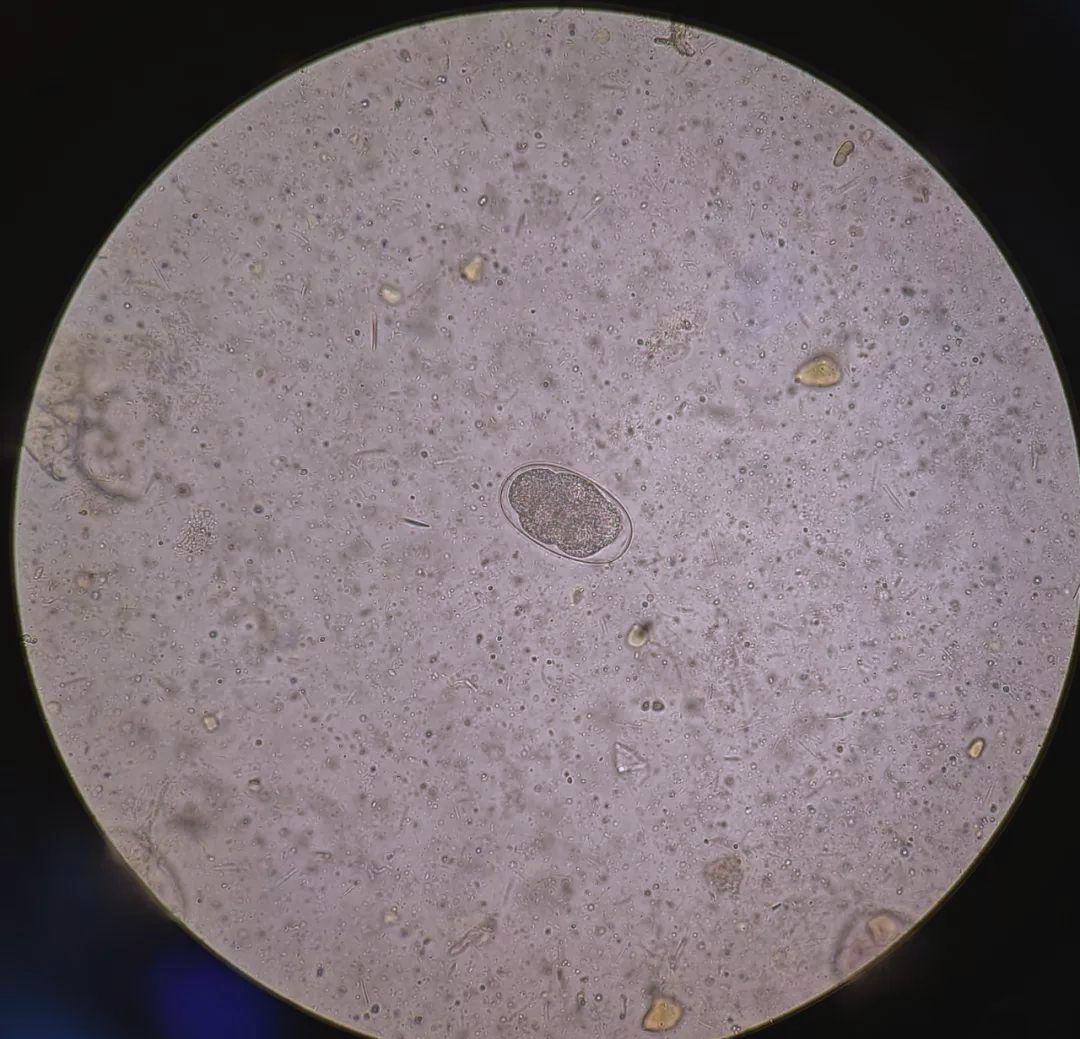

💩粪便常规检查:钩虫卵

钩虫卵:椭圆形,无色透明,大小约

🔍 🔬 钩虫卵,这些微小的生命体,形状为椭圆形,大小在57